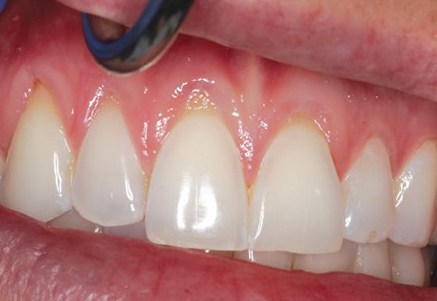

Gengiva Retraída

1) Exposição da raiz ao meio bucal. É fácil notar a coloração um tom mais escuro no seu dente quando existe uma gengiva retraída, essa cor é característica da raiz dentária. Ela não está preparada para ficar exposta em meio bucal, por isso, a agregação de placa bacteriana e o desenvolvimento de cárie pode se mais fácil que na superfície dentária;